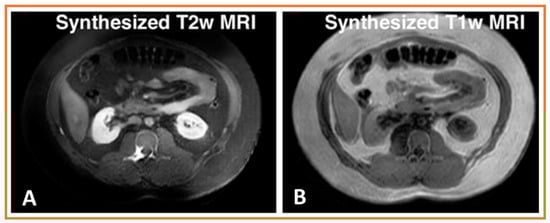

- Deep learning methods can be used to synthesize different contrast modality images for many purposes, including training networks for multi-modality segmentation, image harmonization, and missing modality synthesis.

- AI-based auto-segmentation for discerning abdominal organs is presented here. Deep learning methods can leverage different modalities with more information (e.g., higher contrast from MRI or many experts segmented labeled datasets such as from CT) to improve tumor segmentation performance in a different modality without requiring paired image sets.